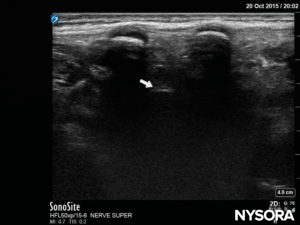

If the patient is an infant, and the bony structures of the vertebral column are not yet fully ossified, a median LAX (Figure 18) provides clear, real-life imaging of the anatomy involved. With this probe position, the spinous process in the image will almost reach the skin (or the top of the US screen). In between the spinous process, the dura mater will be seen as a white double layer; it is found a little less deep than the level at which the posterior complex is found in the SAX (Figure 19).In the paramedian oblique LAX (Figure 20), the transverse process and/or the lamina may be visualized, depending on how far lateral and oblique the probe is placed. The anterior complex is again easily visualized, and most of the time the pia mater can be seen in small children. The characteristic “horse heads” may be found in the image, and the dura mater will be seen in between, at a deeper level (Figure 21). The depth of the dura mater will be more or less equal, as in the SAX and median LAX positions.

FIGURE 19. US image in the median long-axis view, showing the dura (white arrow).